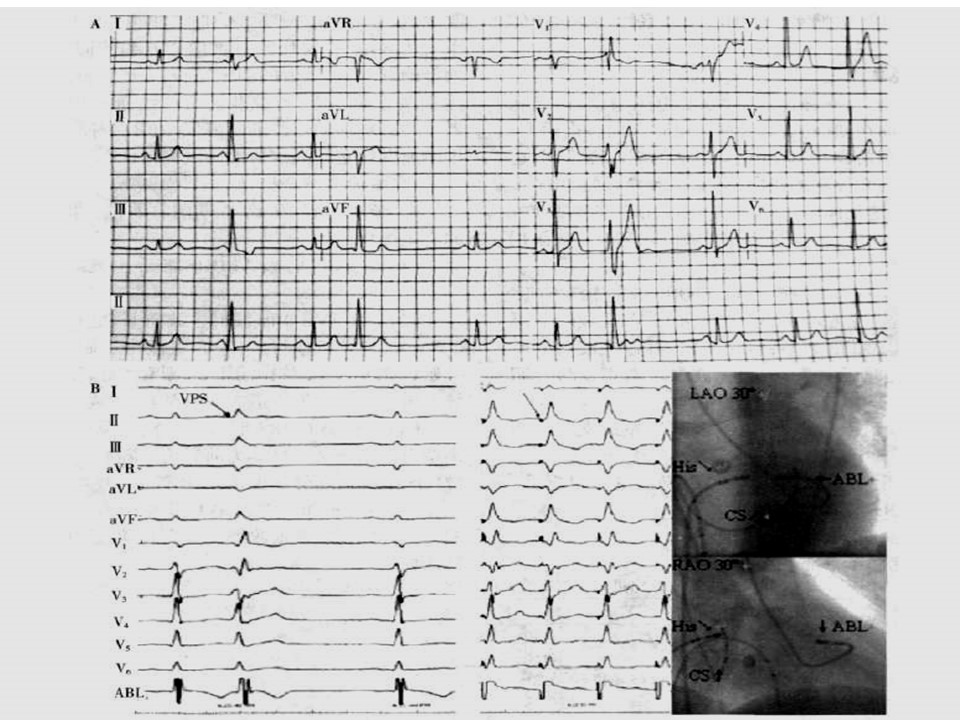

“室性早搏室性心动过速体表心电图定位诊断PPT” 的相关文章